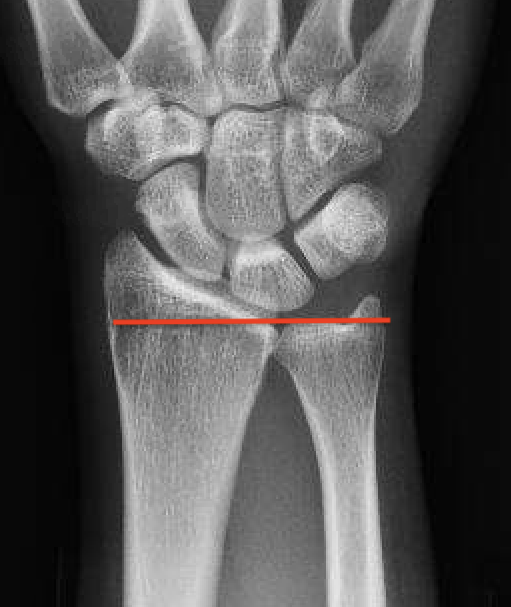

Ulna variance

Supination and pronation alter variance

- varies up to 3 mm with wrist position

- pronation increases ulnar variance

- supination decreases variance

90 / 90 view

- zero rotation view

- neutral supination / pronation

- PA film with wrist in neutral

- elbow 90° / shoulder abducted 90°

Line from lunate fossa and ulna head

- wide variation in population

- mean ulna variance is 1 mm (range 2 - 4)

Ulna neutral

Ulna positive

Ulna negative